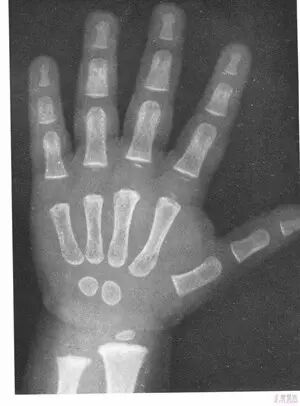

为什么孩子要定期检测骨龄?

骨龄可以真实地反映儿童生长的实际状态。从3岁以后最好每年测定一次骨龄,通过对比骨龄和身高的增长情况,可以准确地分析孩子身高的生长速度和生长潜能,了解孩子未来成年身高状况,对孩子潜能发挥进行有规划性的培养。定期进行骨龄监测,还可以及时发现生长偏离,尽早进行相应的干预。

骨龄评价,需要给孩子拍一张左手的X光片,根据桡骨、尺骨、掌骨、指骨等手部十余个骨的发育程度进行评价。相对于胸部X光片而已,手骨X光片的放射线影响较小,每年拍摄一次手骨X光片,一般不会对孩子的健康构成影响。